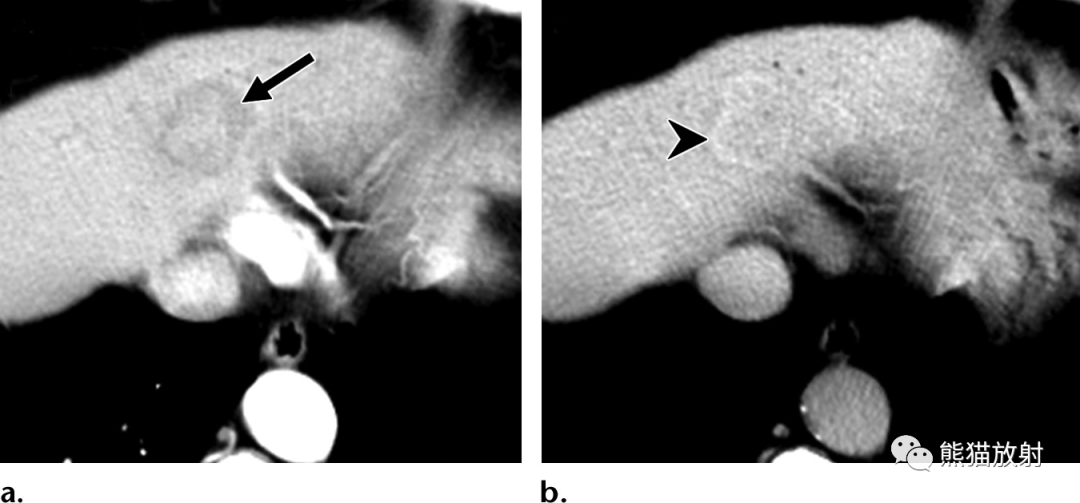

45岁女性,化脓性肝脓肿,表现为发热和胸膜炎性胸痛。(a) 轴位对比增强门脉期CT图像显示肝右叶后段紧贴右侧横膈的多房性囊性肿块。注意壁分层(“双靶征”),内部强化的脓肿膜(箭)被低密度的肝实质水肿(箭头)包围。(b) 轴位增强延迟期CT图像显示内层持续强化,外层延迟强化(箭),多个小房聚集呈“簇征”。